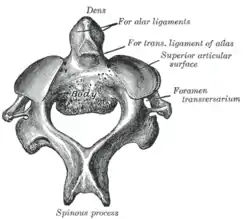

Second cervical vertebra, or epistropheus, from above | |

The axis' defining feature is its strong odontoid process (bony protrusion) known as the dens, which rises dorsally from the rest of the bone.

Dens

The dens, also called the odontoid process, or the peg, is the most pronounced projecting feature of the axis. The dens exhibits a slight constriction where it joins the main body of the vertebra. The condition where the dens is separated from the body of the axis is called os odontoideum and may cause nerve and circulation compression syndrome.[1] On its anterior surface is an oval or nearly circular facet for articulation with that on the anterior arch of the atlas. On the back of the neck, and frequently extending on to its lateral surfaces, is a shallow groove for the transverse atlantal ligament which retains the process in position. The apex is pointed and gives attachment to the apical odontoid ligament. Below the apex, the process is somewhat enlarged and presents on either side a rough impression for the attachment of the alar ligament; these ligaments connect the process to the occipital bone.

The pedicles are broad and strong, especially in the front, where they coalesce with the sides of the body and the root of the odontoid process. They are covered above by the superior articular surfaces.

The vertebral foramen is large, but smaller than the atlas.

The transverse processes are very small, and each ends in a single tubercle. Each process is perforated by the transverse foramen, which is directed obliquely upward and laterally.

The superior articular surfaces are round, slightly convex, directed upward and laterally, and are supported on the body, pedicles, and transverse processes.

The spinous process is large, very strong, deeply channelled on its under surface, and presents a bifurcated extremity.